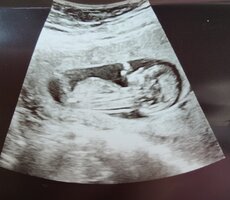

Nub-teorian mukaan sukupuolen voi määrittää jo nt-ultrassa genitaalikyhmyn asennon perusteella. Voit lukea aiheesta lisää täältä.

Kiinnostaako teitä sukupuolen määrittäminen kyseisen teorian avulla? Katsotteko ultrakuvia sillä silmällä?